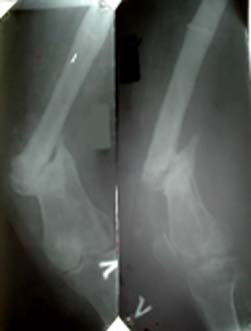

Глубокоуважаемые коллеги.Просьба оказать консультационную помощь Женщина 40 лет. ДТП в 1996: открытый перелом левого бедра, мыщелковый правой голени.

В настоящее время укорочение левой н/конечности 4 см, объем движений левого колена до 70 градусов, патологическая подвижность в области перелома. Планируем дистракцию с помощью аппарата до выравнивания с длиной правой конечности, а вторым этапом резекцию концов отломков бедра и остеосинтез штифтом через интеркондиллярную вырезку.Остеотомию правой б/б кости. Резецированные участки возможно пойдут на заполнение остеотомированной зоны б/берцовой кости. Вопросы по правильности такого планирования, по компоновке аппарата (темп дистракции, жесткость фиксации дистального отломка).Максимов Б.Ю.Сердобск, Пензенская обл.

Резекция здесь - это укорочение, так что лучше подумать, может, о костной пластике? Нельзя ли прислать снимки с чуть большим разрешением?